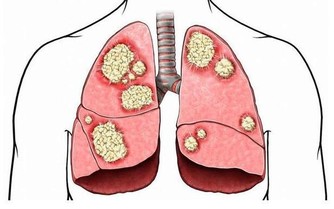

三、肺臟排毒

肺是最容易積存毒素的器官之一。因為人每天的呼吸會將約1000升空氣送入肺中,空氣中飄浮的許多細菌、病毒、粉塵等有害物質也隨之進入肺臟。當然,肺也能通過呼氣排出體內代謝的二氧化碳等廢氣和其他有害入侵者。

肺臟有毒素堆積,會使人經常感冒、咳嗽、哮喘,氣管敏感。中醫認為,肺臟和大腸是一套系統,互為表里。當肺臟有毒素時,腸道內也會有不正常淤積,出現便秘。

肺排毒的時間是凌晨3點到5點。肺臟功能最強的時間是早上7點到9點,此時最好能夠通過運動排毒。在肺功能最強的時候進行慢跑等有氧運動,能強健肺排出毒素的功能。